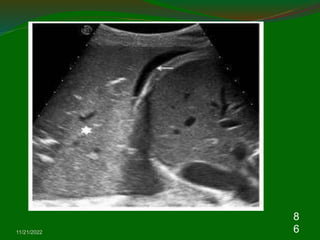

3. Chest wall: Muscle layers, bone, and

pleura

Because air cannot be visualized by US, the

normal lung parenchyma cannot be detected by

US theoretically.

The image of chest US in chest wall including

muscle, fascia, bone, and pleura .

The soft tissue echogenicity with multiple layers

means muscles and fascia.

The normal ribs appear hyperechoic surfaces

with prominent acoustic shadows beneath the

ribs.

11/21/2022

2

7

Approximal 0.5 cm below the ribs shadows,

the visceral and parietal pleura appear as an

enchogenic bright line.

During respiratory movement, the two pleural

lines glide with each other which is referred to

as the “Gliding sign”. Therefore, the “Gliding

sign” means normal parietal and visceral

pleura slide over each other during respiration

and the loss of “Gliding sign” can be seen in

pneumothorax or diffuse pleural thickening